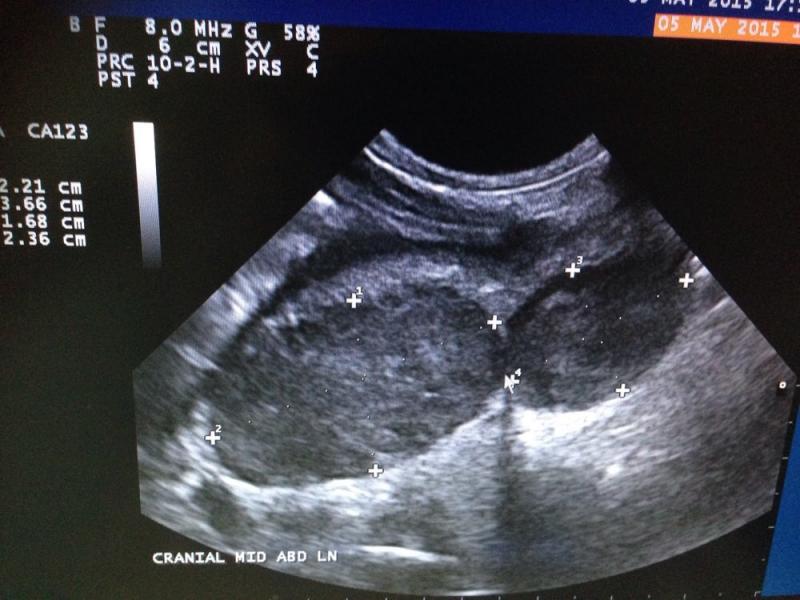

US findings: small pools of free fluid, not possible to sample. Gastric wall thickened, with mixed echogenicity, loss of detail, muscularis and serosa is intact in certain areas. Pyloric appears more normal and lesions seem to extend from fundus to Antrum. Regional LNs are enlarged and some of them very much abnormal in size shape and echostructure. Liver appears diffusely hyperexhoic with 3 focal hypoechoic areas, portal and hepatic veins dilation, GB dissension with abundant sludge and pancreatic region practically unrecognizable; I could not really visualize pancreas. Both adrenals are normal. Kidneys both in close contact with abnormal liver and Ln in right and left quadrants respectively and cranial poles Cortexes appear irregular in echogenicity. Intestines appear to have a good motility and no abnormal layering seen. Oleo exam junction not visualized…

Any ideas? It looks very much like neoplasia to me… So I did FNA but owner didn’t want to sedate and dog only allowed 2 needles. Gastric thickened mucosa is what I got, by the time I wanted to access LNs dog wouldn’t cooperate anymore. My question is… Next time, do I still try and get aspirate from gastric mucosa? Or try some other tissue? I would have chosen LNs first but I didn’t manage to get them superficially accessible after this picture was taken.